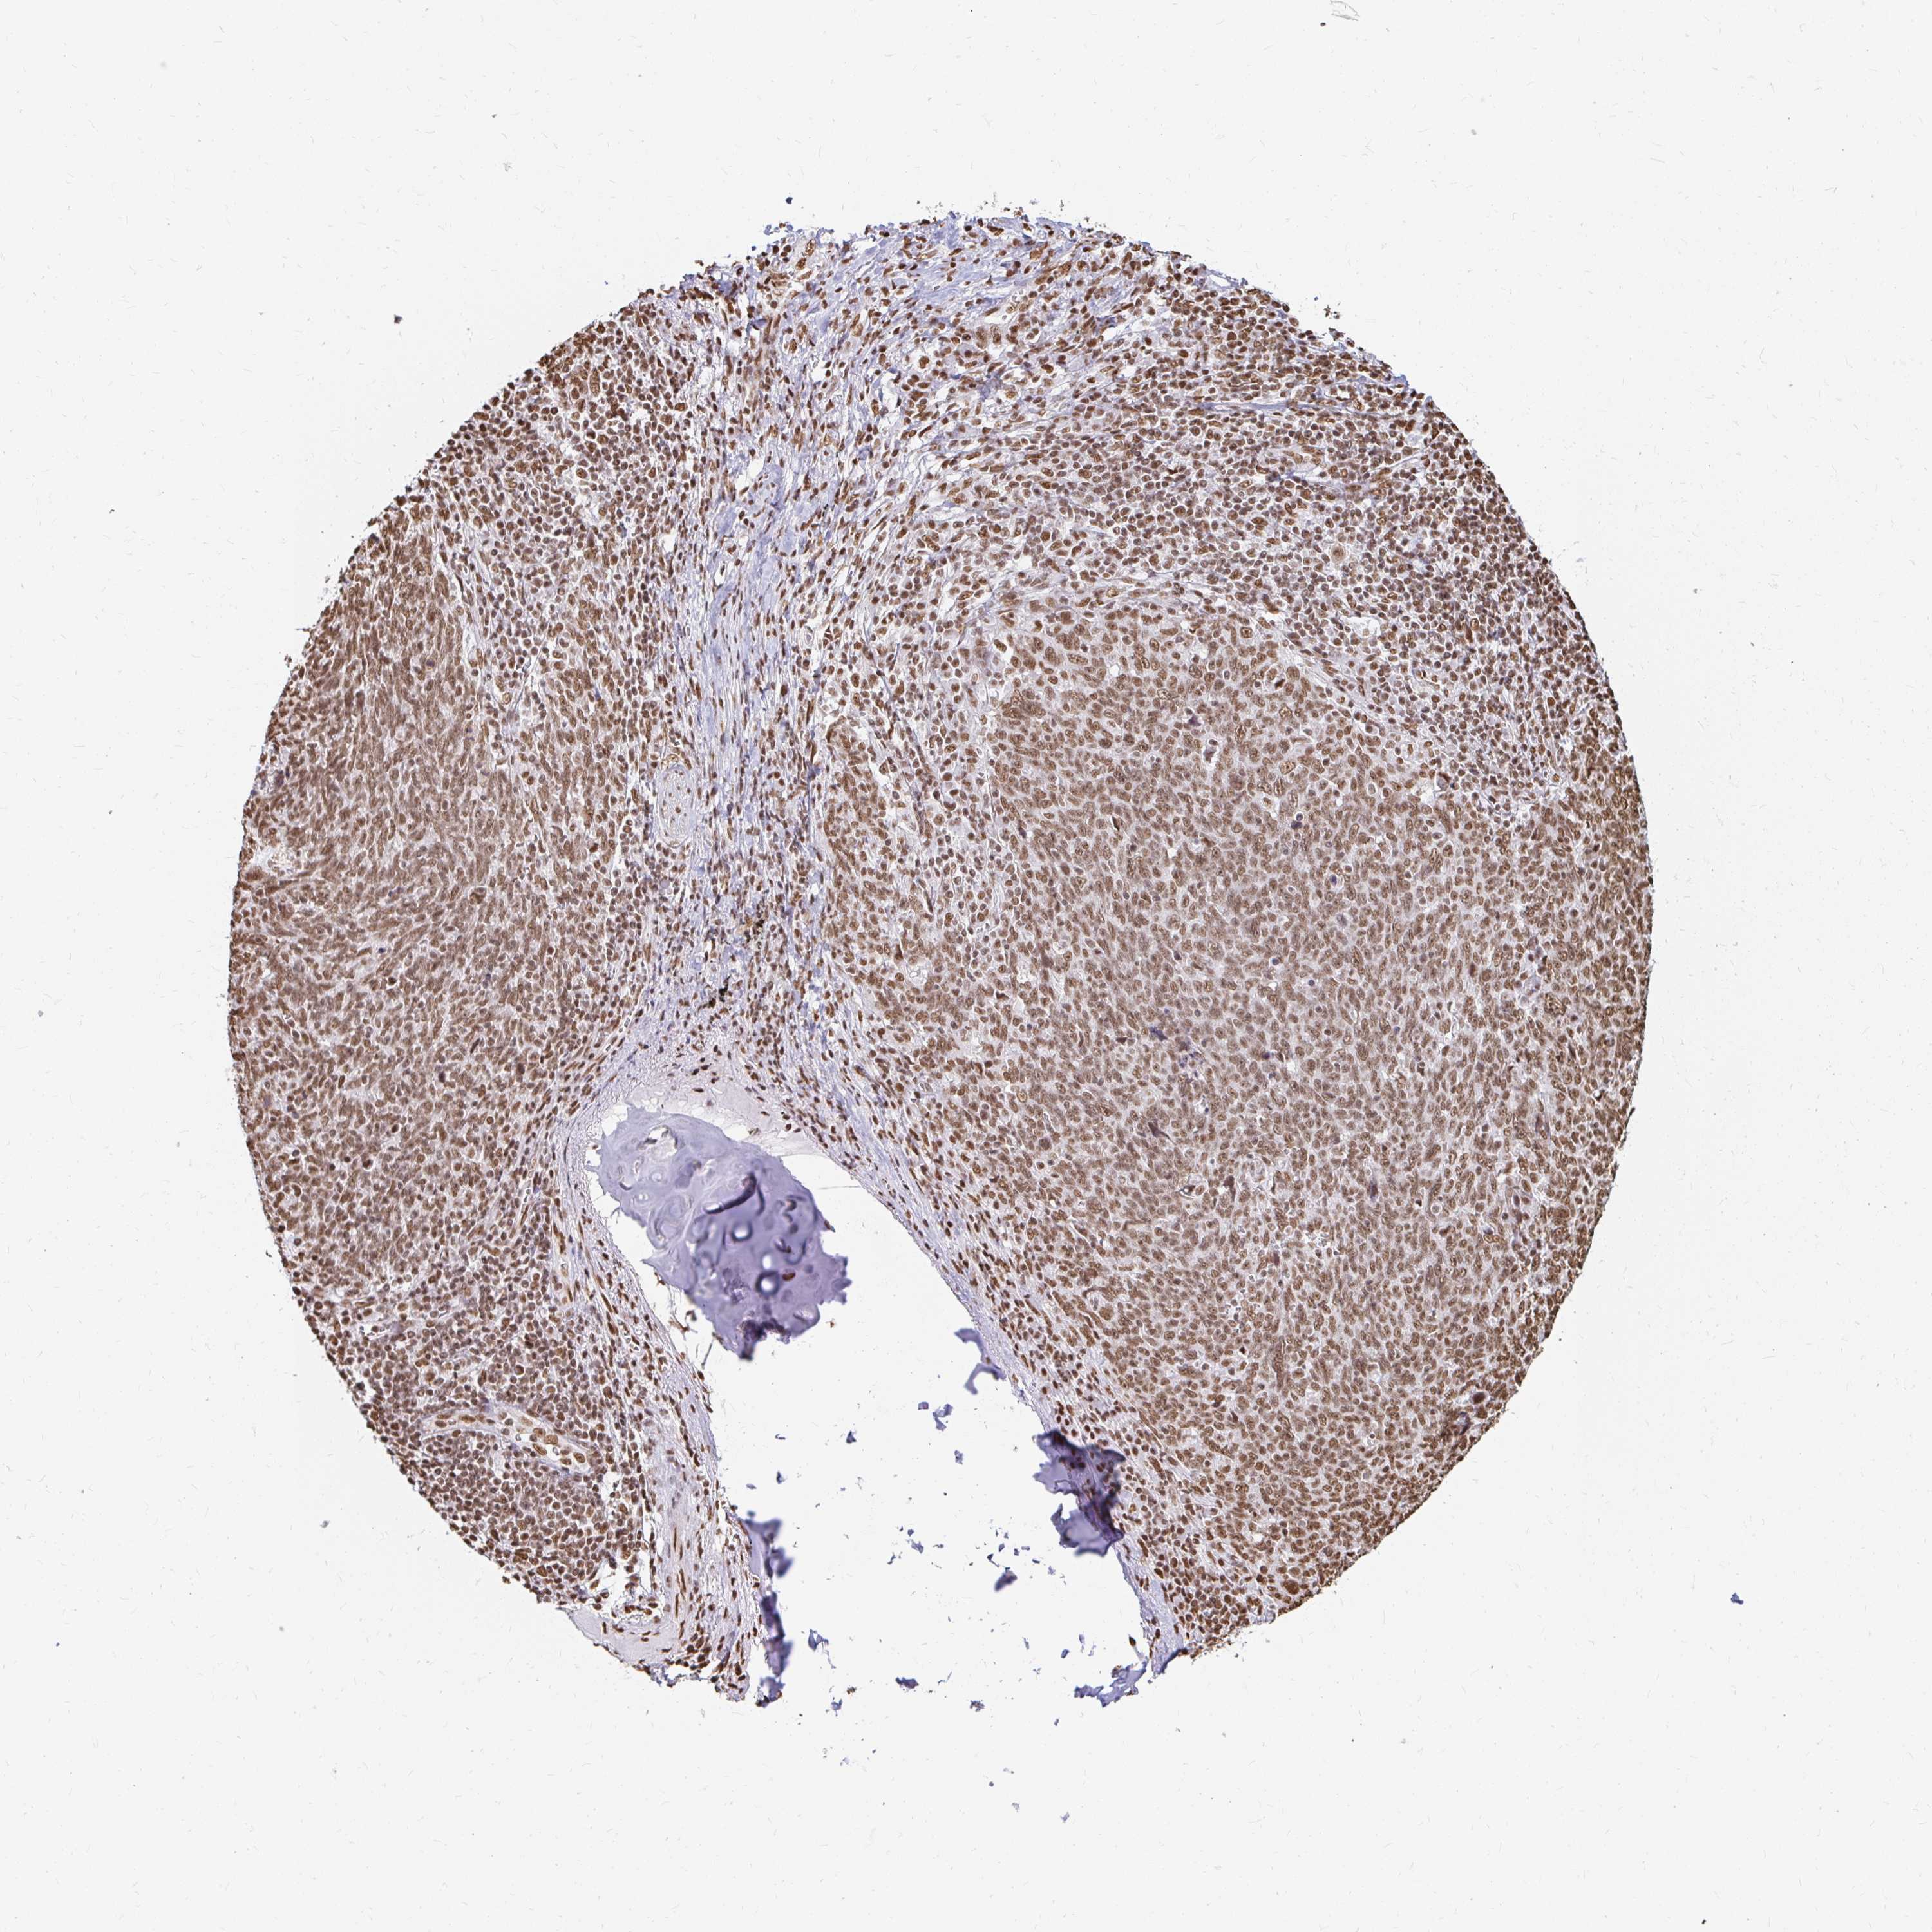

CANCER LUNG CANCER Show tissue menu

HNRNPU is potential prognostic, high expression is unfavorable in Lung Adenocarcinoma (TCGA)

HNRNPU is not prognostic in Lung Adenocarcinoma (validation)

HNRNPU is not prognostic in Lung Squamous Cell Carcinoma (TCGA)